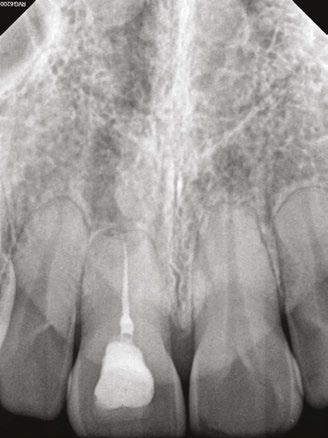

A 48-year-old female patient presented to the graduate endodontic clinic with a referral to evaluate and treat tooth No. 11 through the existing crown. The patient’s chief complaint was, “I was told a year ago I had an infection, but it hasn’t bothered me. They told me I needed a root canal to get rid of the infection.” The patient had no significant health history or any known drug allergies. Dental history for tooth No.11 included multiple restorations followed by a final core and crown in 2019. The adjacent tooth, No. 12, was replaced with an implant in 2018 and restored in 2019, 6 months following final crown of tooth No. 11. Upon examination of records, a periapical radiolucency on tooth No. 11 was visible on the day of crown fabrication and delivery (Figure 1). There was no note of this lesion in the patient’s record. An updated radiograph was taken during a periodic oral exam in September of 2023 showing clear delineation of the periapical radiolucency on tooth No.11 (Figure 2).

Figure 1 (left): Periapical radiograph taken at the time of tooth No. 11 crown delivery in 2018 with a periapical radiolucency extending distally toward implant No. 12. Figure 2 (right): Updated periapical radiograph taken in 2023 during a periodic oral exam showing clear delineation of a periapical radiolucency associated with tooth No. 11

Figure 3: Periapical radiographs taken during endodontic consultation in 2023. Periapical radiolucency originated from tooth No. 11 and extended toward implant No. 12. Calcification was appreciated in the coronal portion of the canal space on tooth No. 11